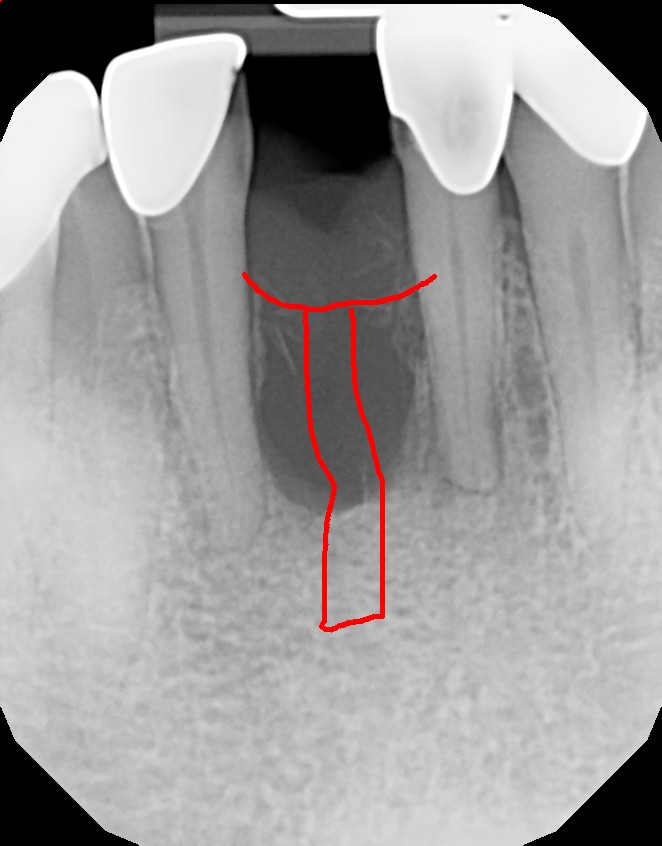

This mouth had recession on just one tooth with very little bone to support the tooth. The area needed support and thickness. The tissue was placed and the area now has thicker tissue to withstand the forces that the patient needs to place on it.